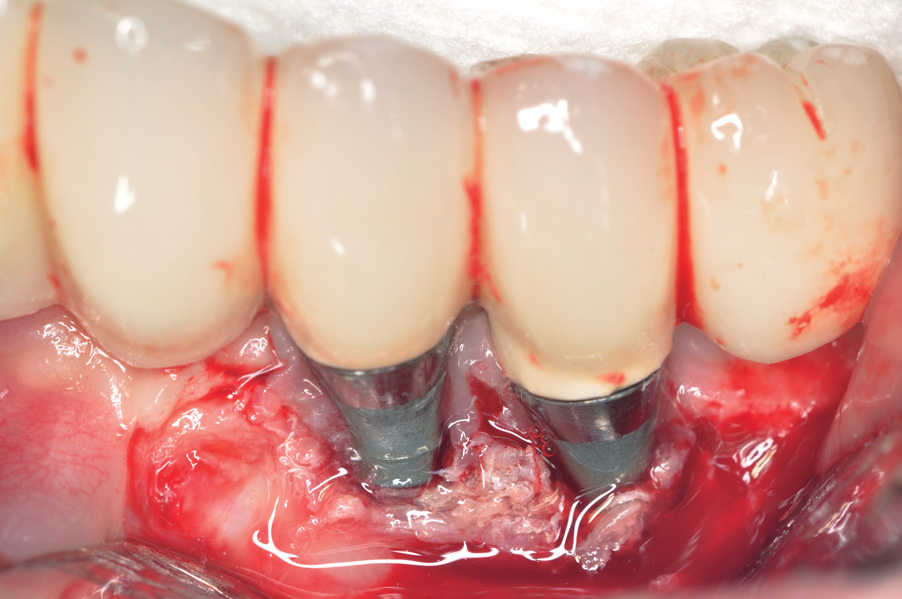

Fig 1. Clinical view of severe gingival inflammation with possible early bone loss present around the implant at the site of the maxillary left first molar. The two premolar implants had mucogingival deformities.

Figure 1

Fig 3. The implants were treated with a Nd:YAG laser. A thrombogenic clot was present at the completion of this treatment.

Figure 3

Dental implants have revolutionized the way in which clinicians treat and restore partially and fully edentulous patients and have demonstrated success for managing a broad range of clinical dilemmas. While implants have been highly predictable and have achieved long-term success, they are not immune from complications associated with improper treatment planning, poor surgical and prosthetic execution, material failure, and inadequate or infrequent maintenance. Among these problems are the biologic complications of peri-implant mucositis and peri-implantitis, which are inflammatory conditions in the soft and/or hard tissues surrounding dental implants (Figure 1 through Figure 4).1,2